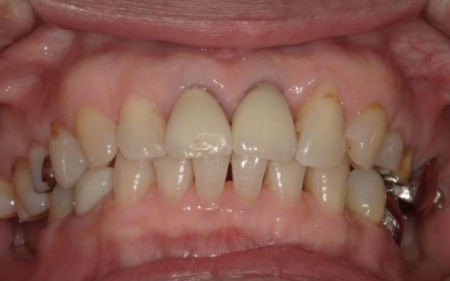

70代女性 歯根が折れた左上奥歯を抜いてインプラント治療で噛み合わせを回復した症例

インプラントが顎の骨と結合したあと、人工歯を装着します。

また、手前の歯にも新しい被せ物を装着しました。

最後に、見た目や噛み合わせに問題がないことを確認し、治療を終了しています。